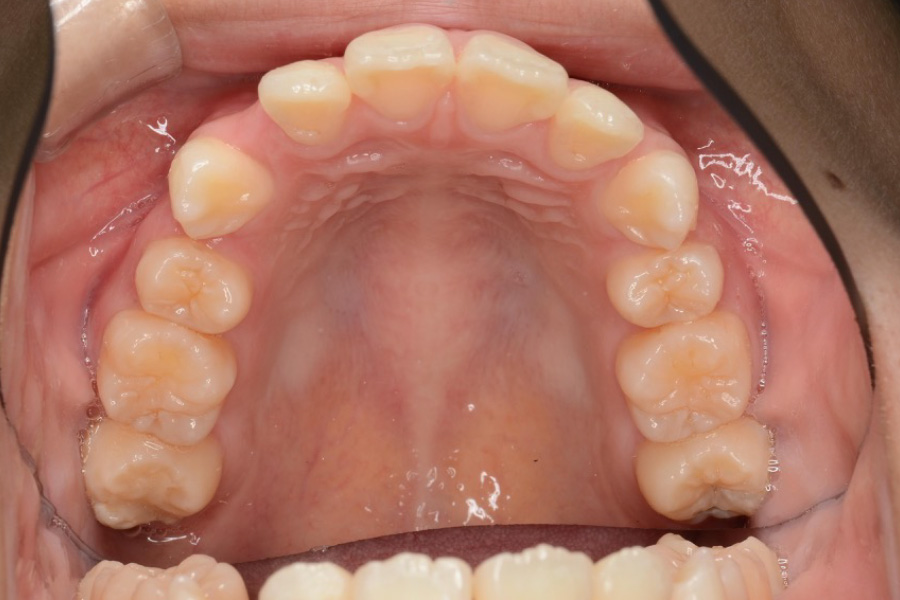

治療前

主訴 歯のスペースを閉じたい

治療内容 インビザライン矯正

非抜歯